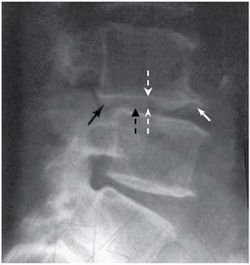

В подавляющем большинстве случаев рентгенологическое исследование, в первую очередь проводящееся для исключения потенциально опасных заболеваний, симптомом которых может быть боль в спине (рис. 8), выявляет также дистрофические изменения позвоночника (остеохондроз) в виде уменьшения межпозвоночных промежутков, субхондрального остеосклероза, формирования остеофитов, кальцификации пульпозного ядра и (или) фиброзного кольца, артроза дугоотростчатых суставов, скошенной формы тел и смещение позвонков (рис. 9). Рентгенография позвоночника помогает в диагностике спондилолистеза (рис. 10), классификация которого основана на степени смещения вышележащего позвонка относительно нижележащего. I степени спондилолистеза соответствует смещение тела позвонка менее чем на 25% его сагиттального размера, II - на 25-50%, III - на 50-75%, IV - на 75-100%. I и II степени относят к умеренно выраженному спондилолистезу.

При рентгенографии с функциональными пробами (сгибание, разгибание в шейном или поясничном отделе позвоночника) возможно выявление ограничения подвижности (функциональной блокады) или гипермобильности (нестабильности) отдельных ПДС (рис. 11).

Строение тел III-VI шейных позвонков отличается тем, что по заднелатеральному их краю формируются так называемые крючки тела позвонка. В норме между ними и телами расположенных выше позвонков находится межпозвоночный диск. При этом крючки тела позвонка препятствуют сдавлению спинномозговых нервов при задней протрузии межпозвоночного диска. Однако по мере уменьшения высоты диска и увеличения размеров крючков они достигают нижней поверхности дуги вышележащего

Отмечается субхондральный остеосклероз (черная пунктирная стрелка), снижение высоты межпозвоночного промежутка (белая пунктирная стрелка), формирование остеофитов (белая стрелка), задний спондилолистез (черная стрелка) позвонка, формируя там неоартроз - унковертебральное сочленение, которое нельзя считать истинным синовиальным сочленением [Д.Г. Боренштейн и др., 2005; П.Л. Жарков, 1994].